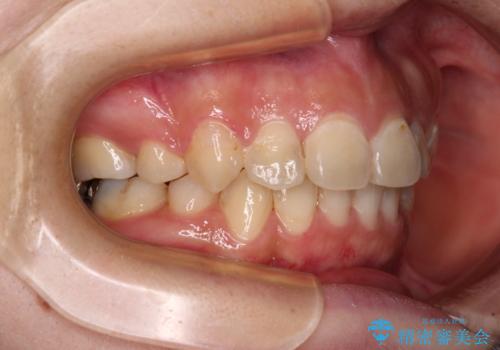

これほど顕著に裏側に隠れいてる歯ですと、仕上がったときに両隣の歯と軸に差が認められることが多いのですが、殆ど違和感のない歯並びを達成することができました。